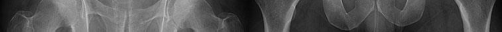

A poly-trauma patient presents hemodynamically unstable with an anteroposterior compression (APC-III) pelvic ring injury. A circumferential pelvic binder is requested to reduce pelvic volume and control hemorrhage. To be anatomically effective, the binder must be centered precisely over which of the following landmarks?

For optimal mechanical advantage and effective reduction of an 'open book' pelvic fracture (APC type), a pelvic binder must be applied directly over the greater trochanters of the femurs. Applying it higher, such as over the iliac crests, is a common error that fails to adequately close the pelvic ring and can paradoxically open the true pelvis.